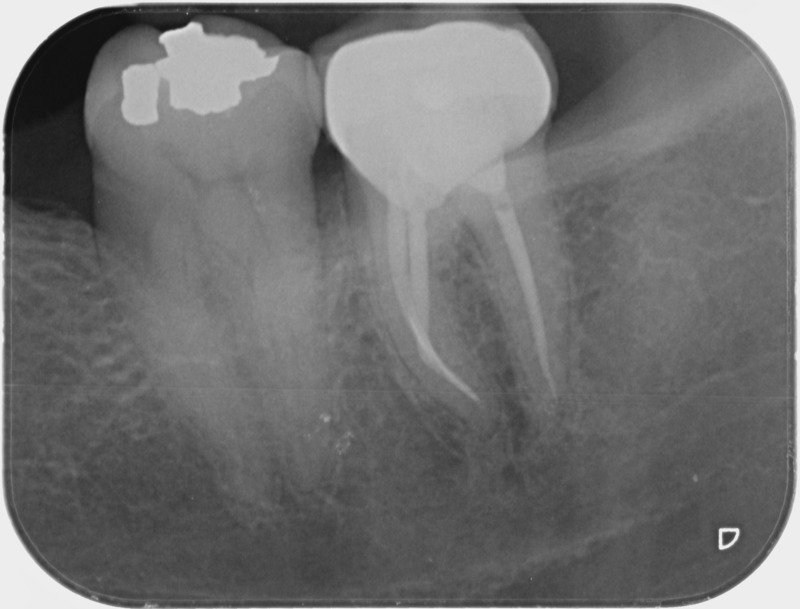

• Traitement endodontique : Sous anesthésie locale et à travers la protection d’un champ opératoire nous accédons à la pulpe de la dent à soigner, puis aux canaux de ses racines que nous devons désinfecter. Ce soin nécessite l’élimination complète de la source de contamination (souvent la carie) parfois sous une ancienne reconstitution ou une couronne qu’il faut alors retirer. Une fois le nettoyage et la mise en forme des canaux réalisés, nous les obturons de façon hermétique avec un ciment et un matériau thermoplastique appelé Gutta Percha. Ceci afin d’empêcher une nouvelle prolifération bactérienne et d’assurer le maintien de la dent dans ses structures de soutien (ligament parodontal et os alvéolaire). L’ouverture effectuée au centre de la dent sera d’abord refermée avec un pansement provisoire avant d’envisager ensemble la reconstitution d’usage : un composite, un inlay-onlay ou une couronne.

Après